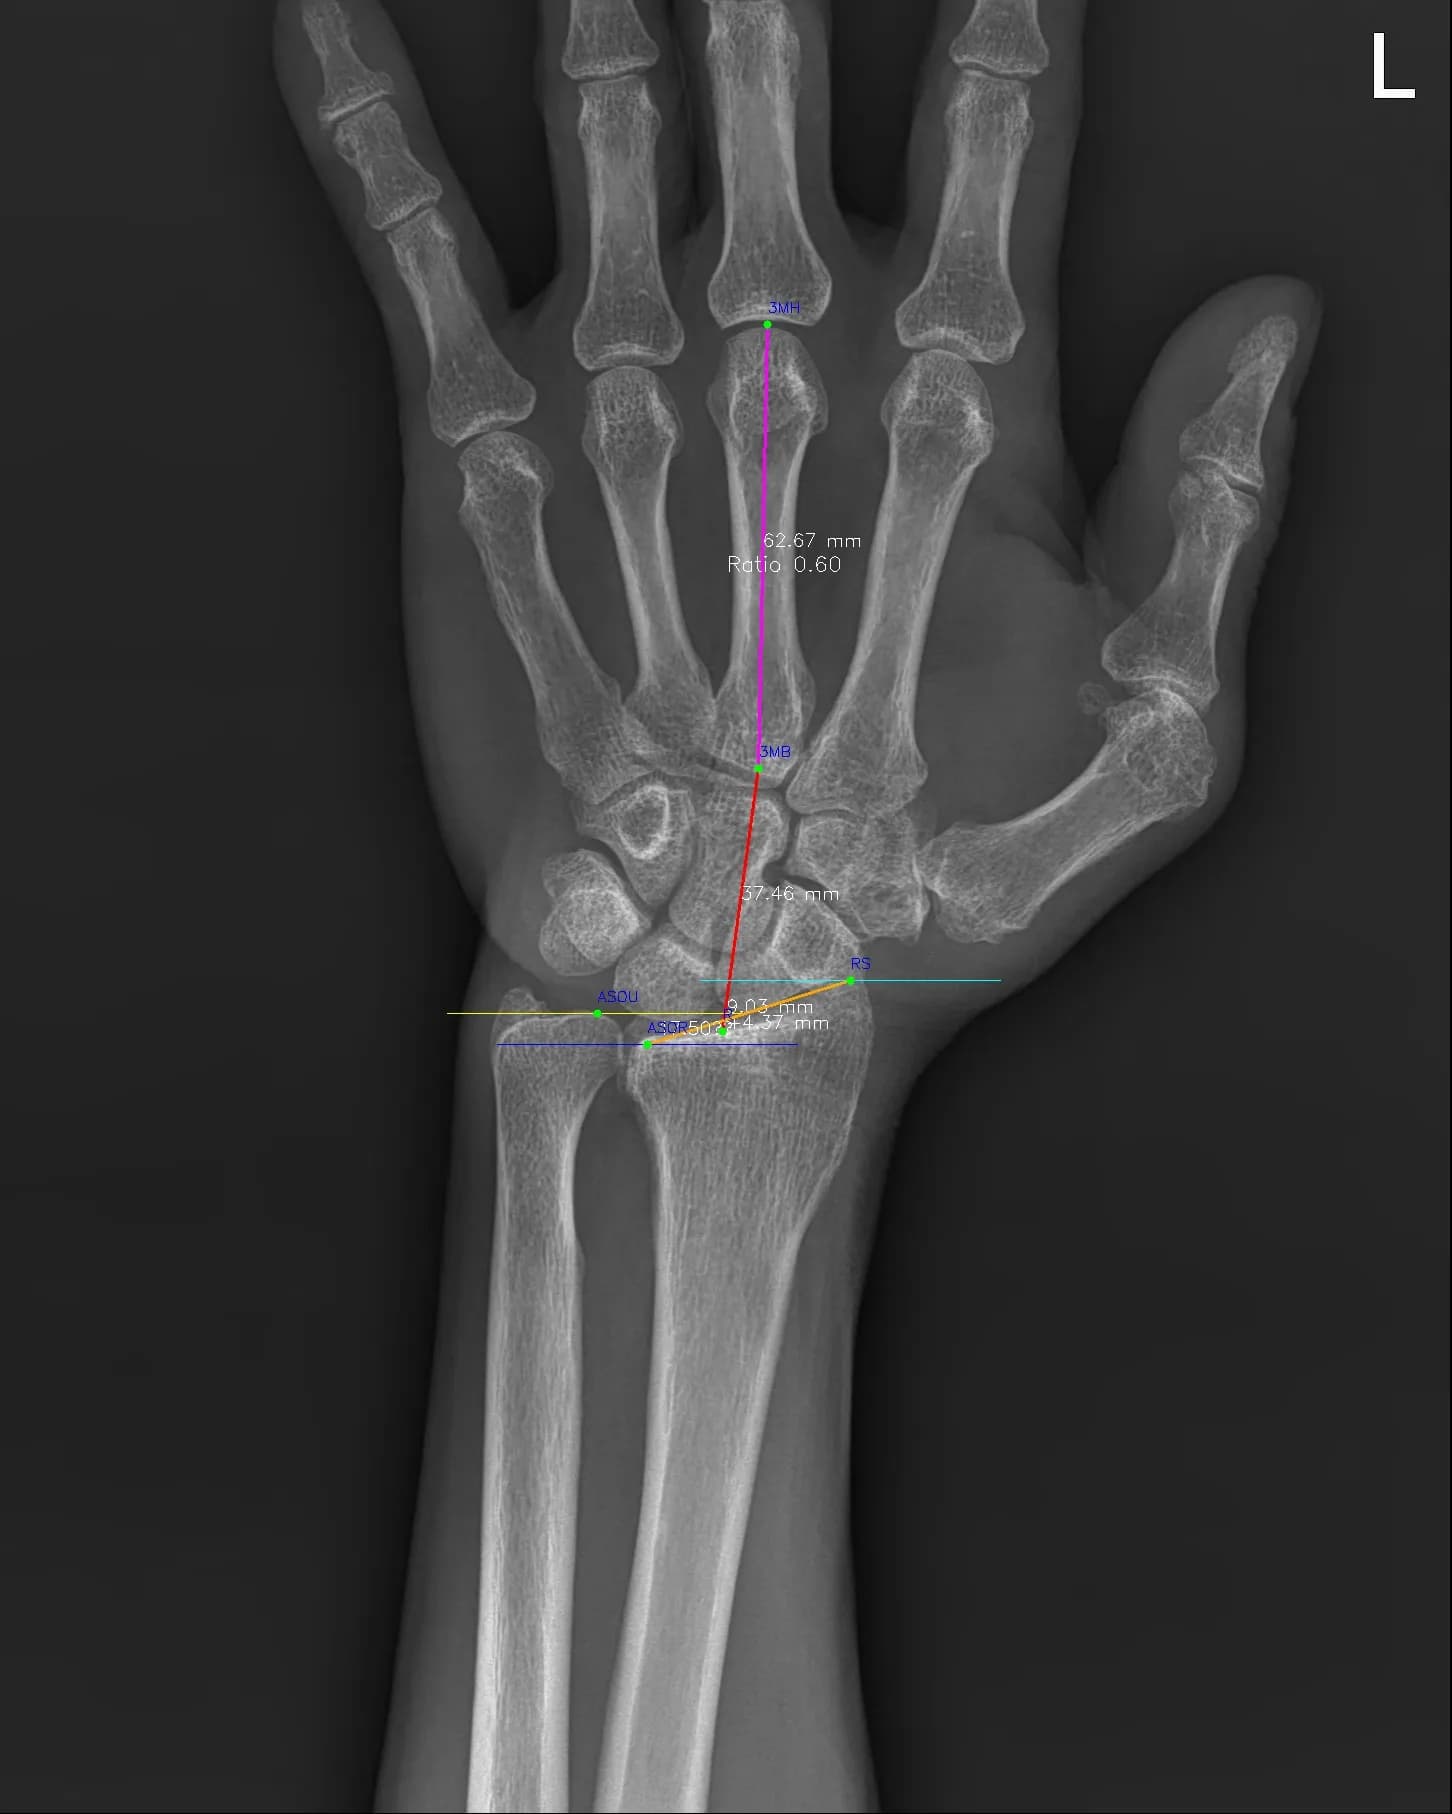

Musculoskeletal X-ray AI Analysis

부위를 클릭하여 결과 이미지를 확인하실 수 있습니다.